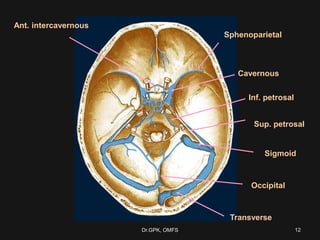

Sphenoparietal

Cavernous

Ant. intercavernous

Sup. petrosal

Inf. petrosal

Transverse

Sigmoid

Occipital

12Dr.GPK, OMFS

Sphenoparietal Cavernous Ant. intercavernous Sup. petrosal Inf.petrosal Transverse Sigmoid Occipital 12Dr.GPK, OMFS